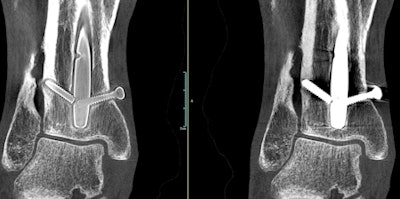

A weight-bearing extremity scan acquired with OnSight 3D. Screw threads are more visible in the image at left after metal artifact correction is applied. Image courtesy of Carestream Health."Our research scientists thought we could leverage that technology for 3D extremity imaging," Titus told AuntMinnie.com. "It was one of those research projects that Carestream allows us to do that may or may not be commercialized."

As development proceeded, Carestream realized it could have a winner on its hands: a compact CBCT scanner capable of being sited in a physician's office that could perform weight-bearing studies not possible on existing whole-body CT scanners. Carestream received 510(k) clearance from the U.S. Food and Drug Administration (FDA) for its OnSight 3D scanner in August 2016, and shipments are scheduled to begin by the end of this year.

OnSight 3D is designed to bring advanced imaging to the orthopedic physician office segment, which up to now has mostly made do with x-ray. It includes image processing algorithms optimized for orthopedic use, such as fast 3D rendering and metal artifact reduction.